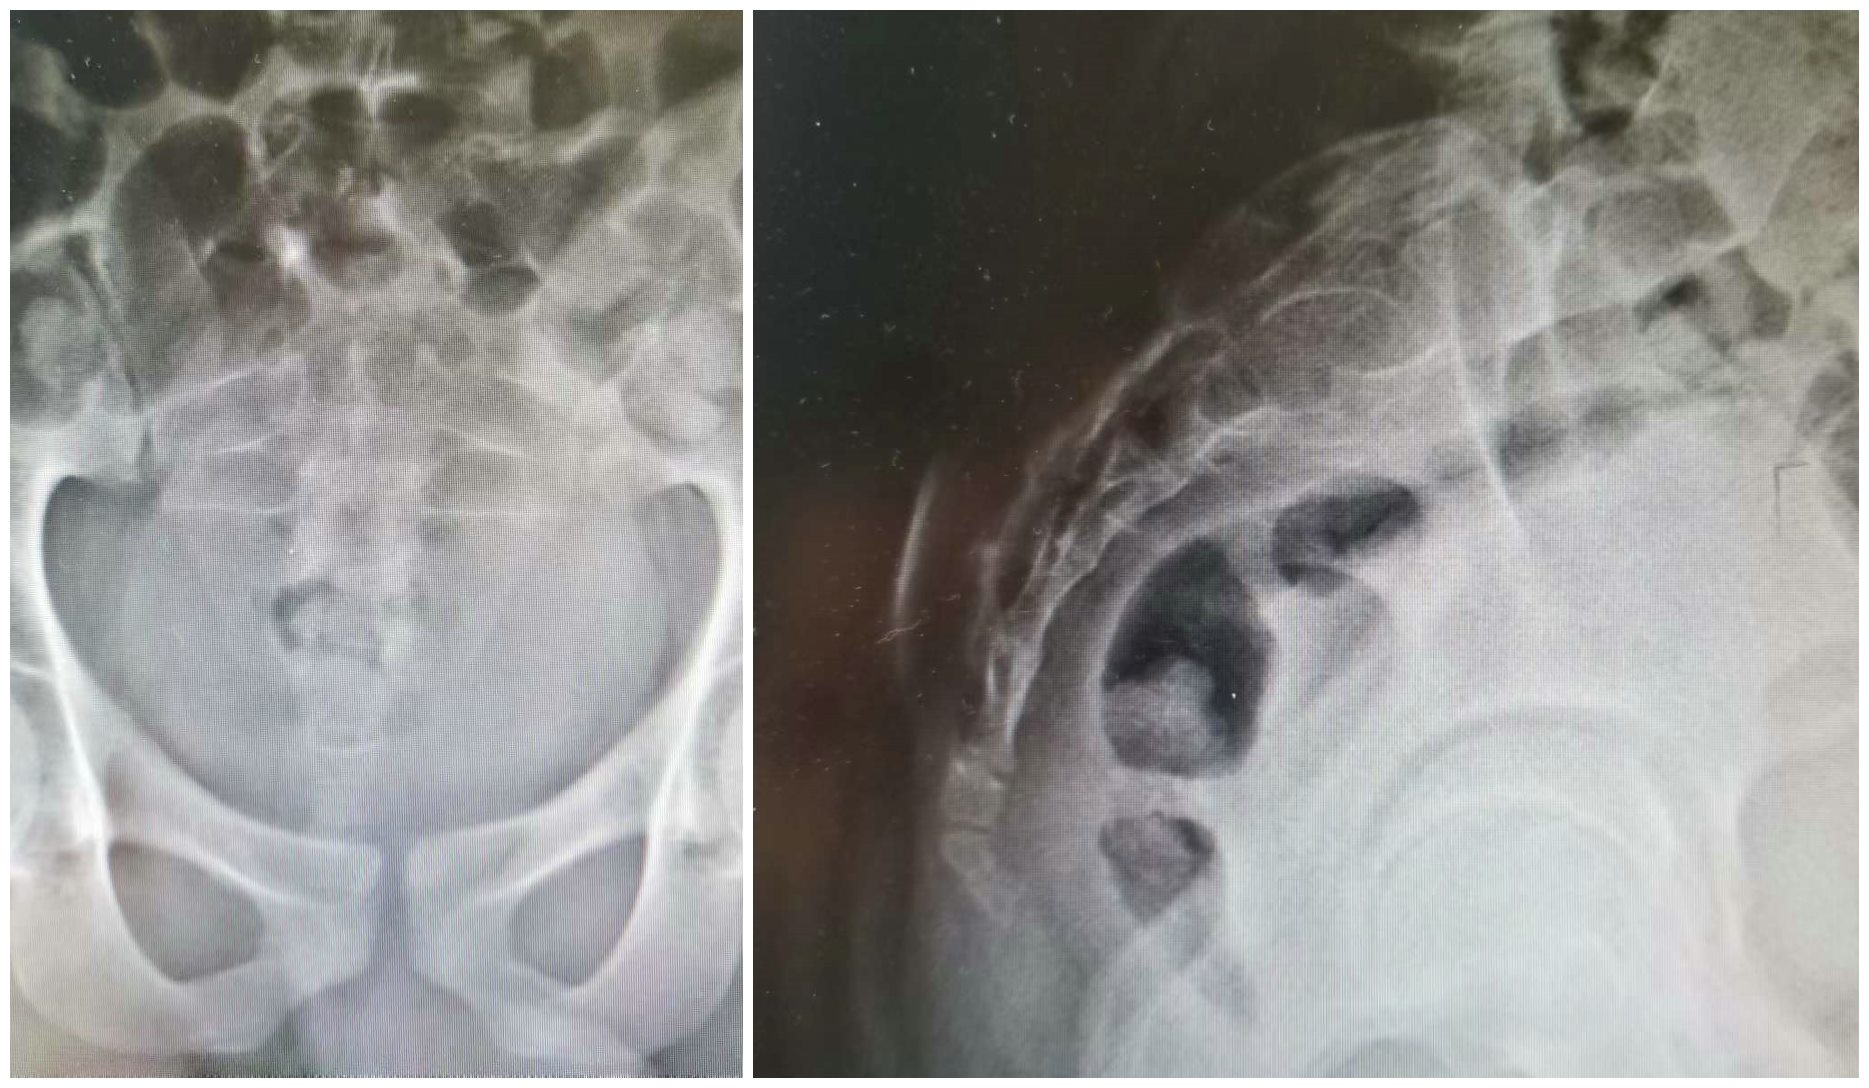

王旭主任团队仔细分析病情,全面评估和讨论后,制定了详细周密的手术计划并成功实施。即术前使用地舒单抗诱导瘤体纤维化、体积缩小,边界清晰化,血运减少,术中采用微波消融进一步灭活肿瘤细胞,减少瘤体血运,最后刮除植骨的手术方案。术中视野清晰,出血小于100ml,瘤体刮除彻底,有效保护了骶神经。术后患者症状明显缓解(图片4),术后病理显示经应用术前地舒单抗诱导联合术中微波消融技术,ki67降至30%,效果明显(图片3)。术前应用地舒单抗诱导联合术中微波消融技术,进行高位骶骨骨巨细胞瘤的低出血量手术治疗的方案,为骶骨GCT的治疗开辟了新的思路和方法,将造福于更多患者。

图4 术后X线片